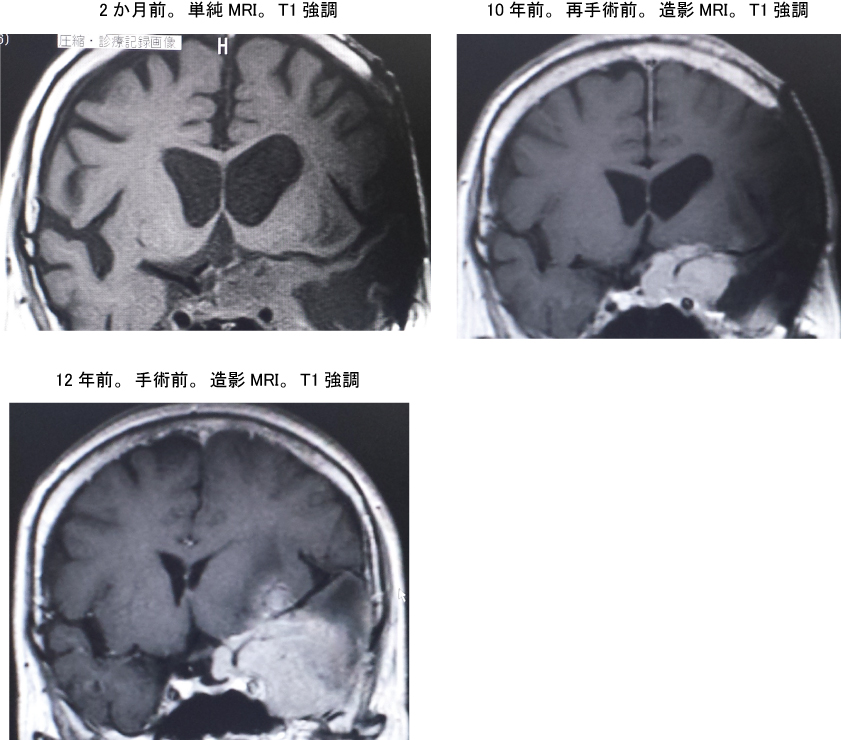

@73ÎB—«B16”N‘OA‹ô”“I‚É‘–ŒŽîŽw“EB12”N‘OAŠJ“ªŽèpBp’¼Œã‚æ‚è¶“®Šá_Œo–ƒáƒA¶Ž‹—͒ቺBŽîᇑ‘åAŽ‹—͒ቺ‘ˆ«‚µA10”N‘OAÄŽèpŒãƒTƒCƒo[ƒiƒCƒtB¶Ž‹—Í‚ÍÁޏ‚µ‚½B1”N‘OAŒŒ´Na 135mEq/LB4‚©ŒŽ‘OAˆÓޝÁޏ‚Å‹~‹}”À‘—‚³‚êANa 116mEq/LBSIADH‹^‚¢‚Ìf’fB2‚©ŒŽ‘OA•›t•s‘S‚Ìf’f‚ŃR[ƒgƒŠƒ‹•â[B

<‰æ‘œŠŒ©>